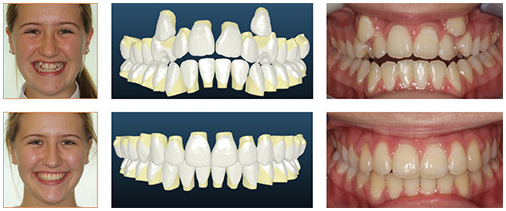

廊坊圣洁口腔高效矫正深覆合,缩短37%矫治时间

圣洁口腔针对深覆合牙齿不齐症状,采用整体移动控根技术,高效排齐牙齿,配合微笑曲线定制技术,让牙齿整齐的同时,拥有完美笑容曲线,牙美脸型更美! 》》》相关阅读:在廊坊,哪些人做隐形矫正比较好?

整体移动控根技术是以控制根部为核心的移动,是通过牙冠与牙根整体受力,使牙齿各结构部位协调同步移动得以矫正,避免了常规正畸方式带来的牙齿倾斜、牙根松动等问题,同时为牙齿提供稳固的根基,以确保正畸效果能长久稳定、宛如天生。